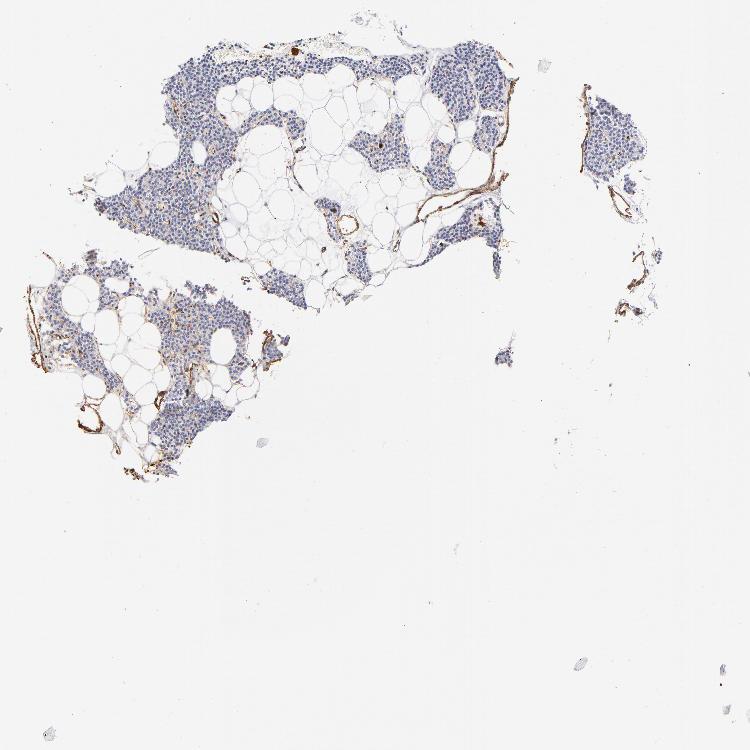

TISSUE PRIMARY DATA PARATHYROID GLAND Show tissue menu

PARATHYROID GLAND - Antibody stainingi

Antibody staining in the annotated cell types in the current human tissue is reported as not detected, low, medium, or high, based on conventional immunohistochemistry profiling in selected tissues. This score is based on the combination of the staining intensity and fraction of stained cells.

Each image is clickable and will lead to virtual microscopy that enables deeper exploration of all samples and also displays staining intensity scores, fraction scores and subcellular localization as well as patient and tissue information for each sample.

Antibody HPA001115Antibody HPA002925Antibody CAB000356

Glandular cells Not detectedNot detectedNot detected